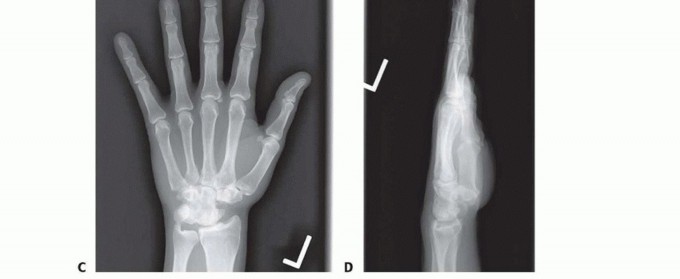

FIG 1 • Nine-year follow-up of four-corner fusion. A,B. Maximal active wrist extension and flexion. C,D. AP and lateral radiographs.Stage III SLAC arthritis can be managed with either a four-corner fusion or a proximal row carpectomy with dorsal capsular interposition.28In patients 35 years of age or younger at the time of proximal row carpectomy, subjective and objective function may decline over time, and they may eventually require a wrist fusion.28Circular plate fixation for CHLT fusion is a newer trend. Weiss et al34 reported a union rate approaching100% and high patient satisfaction.14 However, several subsequent studies have documented higher nonunion rates, higher hardware failure rates, higher pain scores, and an overall lower rate of patient satisfaction compared to other traditional methods of fixation.8,16,25,29Recently, use of a locked radiolucent polyetheretherketone (PEEK) circular plate has shown union in 92% of patients, 66% ROM and 70% grip strength compared to contralateral, and good functionaloutcomes.21Biomechanical analysis of four-corner fusion with Kirschner wires versus dorsal circular plate versus locking dorsal circular plate showed that dorsal locked plates were significantly more stable.17At an average of 67-month follow-up, patients with lunate excision and STT fusion for lunate collapse due to Kienböck disease maintained motion and pain relief, although the scaphoid had a tendency to shift toward the lunate fossa, suggesting a risk of progression to radioscaphoid arthritis if the lunate isexcised.19Scaphocapitate arthrodesis for chronic scapholunate instability in manual laborers has shown an 87 degrees arc in flexion/extension and 41 degrees arc in radioulnar deviation, with 60% of normal grip strength and maintained pain reduction with 90% return to work rate at 10-year follow-up. Incidence ofradiocarpal arthritis was 30%.22In a small series, capitolunate arthrodesis with tricortical iliac crest bone graft, proximal pole scaphoid excision, distal pole scaphocapitate fusion, and radial styloidectomy lead to 100% union rate and 70% Mayo wrist score at 4-year follow-up.15Capitolunate arthrodesis has shown a decrease of 25 degrees from preoperative and loss of 6-kg strength, allowing a pain-free and functional wrist in 8 of 11 patients reviewed at 10-year follow-up.12 Four-corner fusion with headless screw technique resulted in 94% union with average flexion-extension arc of 71 degrees, maintained carpal height, and 80% grip strength.24